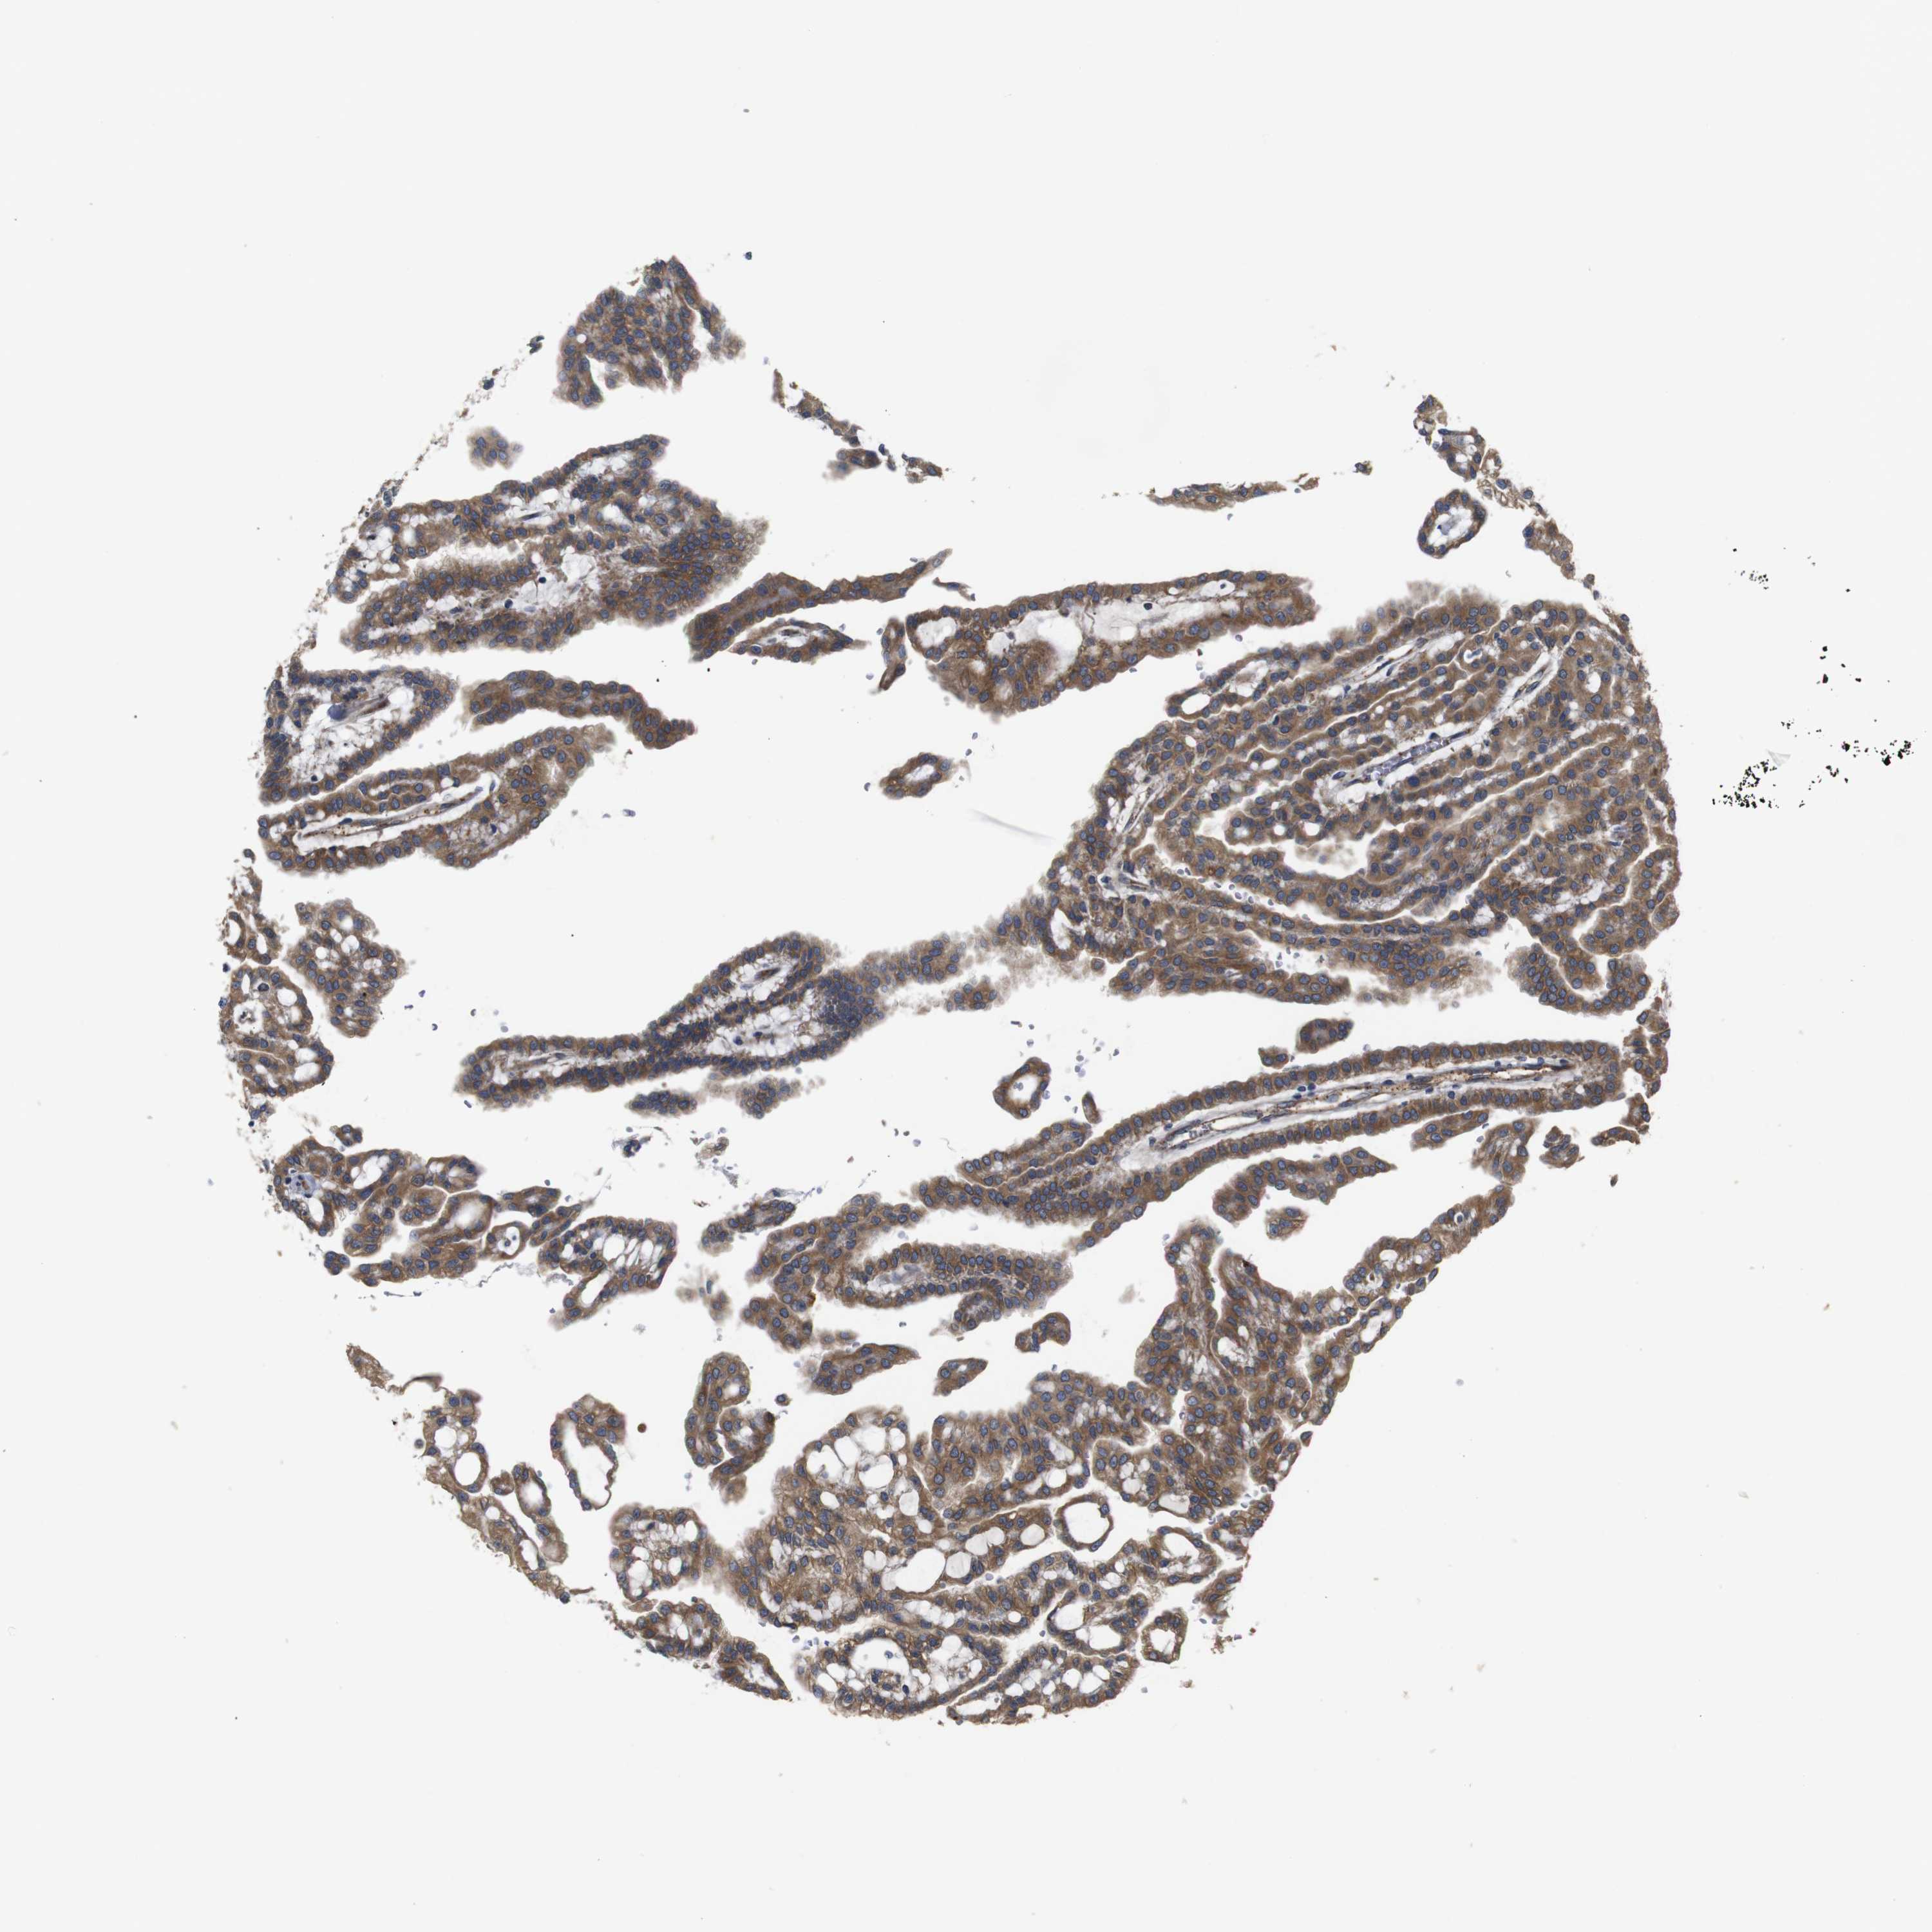

KIDNEY RENAL PAPILLARY CELL CARCINOMA (TCGA) - Interactive survival scatter ploti

The Survival Scatter plot shows the clinical status (i.e. dead or alive) for all individuals in the patient cohort, based on the same data that underlies the corresponding Kaplan-Meier plots. Patients that are alive at last time for follow-up are shown in blue and patients who have died during the study are shown in red.

The x-axis shows the expression levels (FPKM) of the investigated gene in the tumor tissue at the time of diagnosis. The y-axis shows the follow-up time after diagnosis (years). Both axes are complimented with kernel density curves demonstrating the data density over the axes. The top density plot shows the expression levels (FPKM) distribution among dead (red) and alive patients (blue). The right density plot shows the data density of the survived years of dead patients with high and low expression levels respectively, stratified using the cutoff indicated by the vertical dashed line through the Survival Scatter plot. This cutoff is automatically defined based on the FPKM cutoff that minimizes the p-score. The cutoff can be changed by dragging the vertical line or by entering a cutoff value in the square labeled "Current cut-off".

Under the Survival Scatter plot the p-score landscape (black curve; left axis) is shown together with dead median separation (red curve; right axis). Dead median separation is the difference in median mRNA expression between patients who have died with high and low expression, respectively. It is calculated as follows: median FPKM expression of dead patients with high expression - median FPKM expression of dead patients with low expression. This is intended to aid the user in visually exploring custom cutoffs and the associated p-scores and dead median separation.

Individual patient data is displayed and can be filtered by clicking on one or more of the category buttons on the top of the page. Categories describing expression level and patient information include: high, low, alive, dead, female, male and tumor stages. The scale of the x-axis can be toggled between linear and log-scale by clicking on the "x log" button. Mouse-over function shows TCGA ID, patient information and mRNA expression (FPKM) for each patient.

& Survival analysisi

Kaplan-Meier plots summarize results from analysis of correlation between mRNA expression level and patient survival. Patients were divided based on level of expression into one of the two groups "low" (under cut off) or "high" (over cut off). X-axis shows time for survival (years) and y-axis shows the probability of survival, where 1.0 corresponds to 100 percent.

UBE2G2 is not prognostic in Kidney Renal Papillary Cell Carcinoma (TCGA)

Best expression cut offi

Median expression refers to the median FPKM value calculated based on the gene expression (FPKM) data from all patients in this dataset. When clicking on this number, the vertical dashed line indicating cut-off, the interactive survival plot, and the Kaplan-Meier curve will be adjusted to show results based on the median expression.

: N/A

Median follow up timei

Median follow up time refers to the median time (years) after diagnosis with this type of cancer, based on clinical data from all patients in this dataset.

P scorei

Log-rank P value for Kaplan-Meier plot showing results from analysis of correlation between mRNA expression level and patient survival.

N/A

5-year survival highi

5-year survival for patients with higher expression than the expression cutoff.

For melanoma and glioma, 3-year survival is shown.